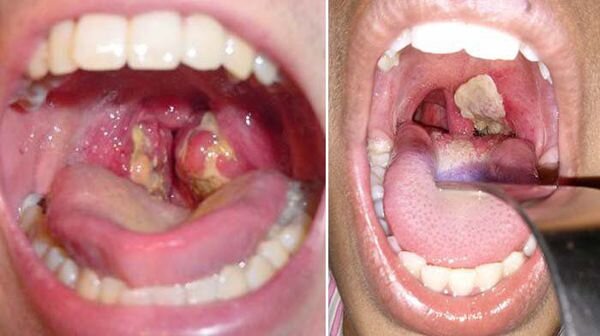

Дифтерия зева

Основные клинические симптомы, которые позволяют заподозрить локализованную дифтерию зева, сводятся к следующему: ведущим симптомом является фибринозный выпот на миндалинах, плотный, блестящий, сероватого цвета, трудно снимающийся. У привитых он может быть тонким недостаточно гомогенным, более плотным и блестящим, лишь на отдельных участках может довольно свободно и без кровотечения сняться, частично растираться. И тем не менее: сохраняется определенное соотношение между отдельными проявлениями местного процесса, т.е. если выпот больше на одной миндалине, то эта же миндалина более отёчна, чем вторая, где налет меньше.

Поэтому, сплошной налет без заметного увеличения размеров миндалин является одним из доводов против дифтерии. Необходимо обратить внимание на характер гиперемии, которая при дифтерии не разлитая, а больше выражена вокруг налетов и области прилегающих передних дужек. Гиперемия язычка и прилегающих к нему тканей мягкого нёба не характерна для дифтерии.